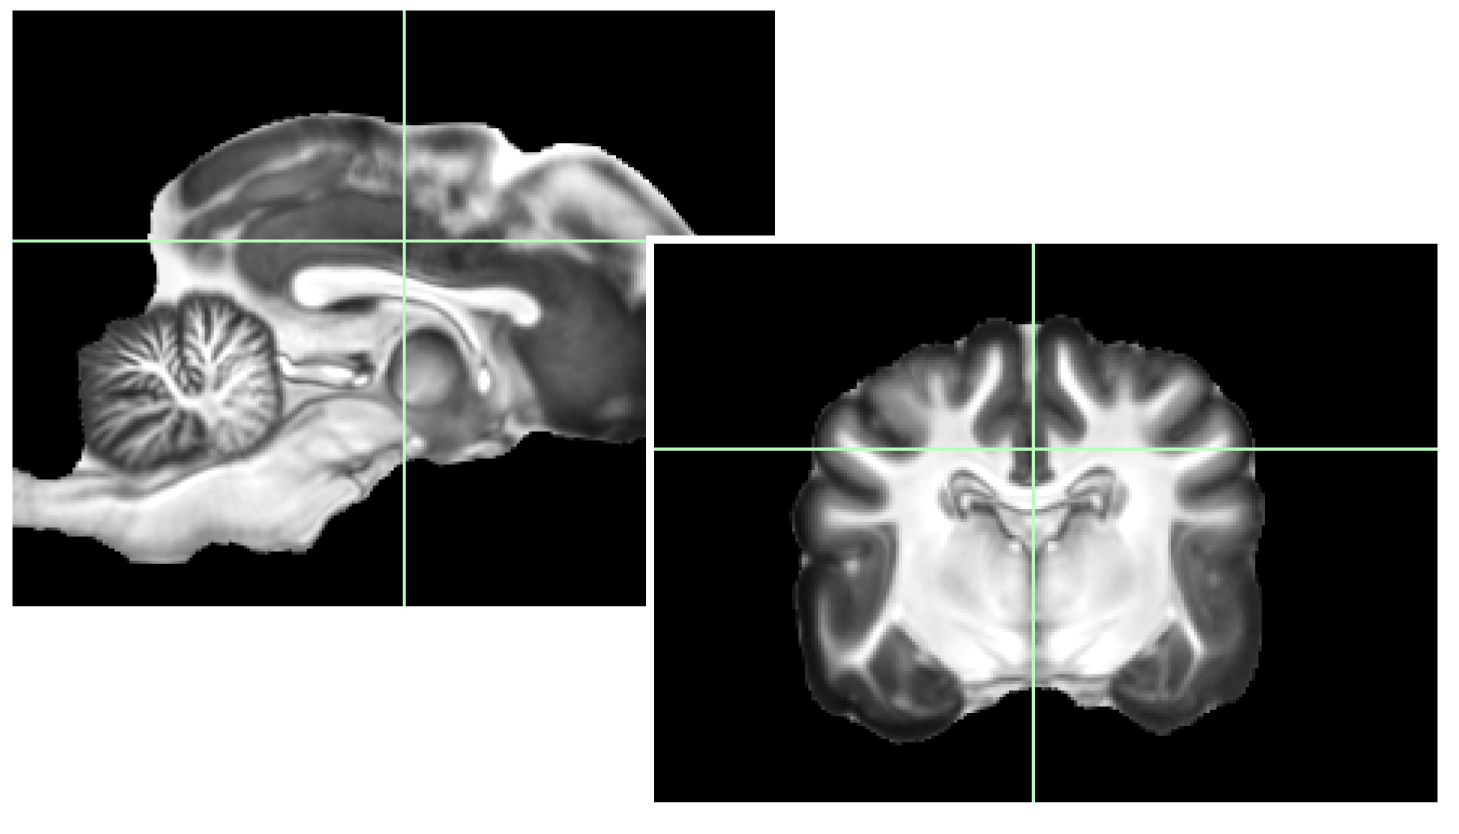

Mri Anatomy Dog . canine brain mri & brain tissue atlas presents transverse views of a beagle brain obtained by magnetic resonance imaging. in the last few years, anatomical and functional magnetic resonance imaging (mri) studies of awake. this web site presents mri images of the canine head, neck, thorax, abdomen, & pelvis, viewable in transverse, sagittal & dorsal. For everyone who needs to learn (or relearn) imaging neuroanatomy , there is an excellent new. mri brain atlas. this web app atlas is intended for veterinary students and radiologists seeking quick access to canine brain anatomy through a mobile device. canine brain mri & brain tissue atlas presents transverse views of a beagle brain obtained by magnetic resonance imaging.

For everyone who needs to learn (or relearn) imaging neuroanatomy , there is an excellent new. mri brain atlas. this web site presents mri images of the canine head, neck, thorax, abdomen, & pelvis, viewable in transverse, sagittal & dorsal. canine brain mri & brain tissue atlas presents transverse views of a beagle brain obtained by magnetic resonance imaging. this web app atlas is intended for veterinary students and radiologists seeking quick access to canine brain anatomy through a mobile device. canine brain mri & brain tissue atlas presents transverse views of a beagle brain obtained by magnetic resonance imaging. in the last few years, anatomical and functional magnetic resonance imaging (mri) studies of awake.

Mri Anatomy Dog mri brain atlas. in the last few years, anatomical and functional magnetic resonance imaging (mri) studies of awake. this web site presents mri images of the canine head, neck, thorax, abdomen, & pelvis, viewable in transverse, sagittal & dorsal. mri brain atlas. canine brain mri & brain tissue atlas presents transverse views of a beagle brain obtained by magnetic resonance imaging. canine brain mri & brain tissue atlas presents transverse views of a beagle brain obtained by magnetic resonance imaging. this web app atlas is intended for veterinary students and radiologists seeking quick access to canine brain anatomy through a mobile device. For everyone who needs to learn (or relearn) imaging neuroanatomy , there is an excellent new.

Canine Brain MRI Atlas 20130233 University of Minnesota Office for Technology Commercialization Mri Anatomy Dog this web site presents mri images of the canine head, neck, thorax, abdomen, & pelvis, viewable in transverse, sagittal & dorsal. in the last few years, anatomical and functional magnetic resonance imaging (mri) studies of awake. this web app atlas is intended for veterinary students and radiologists seeking quick access to canine brain anatomy through a mobile. Mri Anatomy Dog.

Canine Brain MRI Atlas Veterinary Radiology normal anatomy vetAnatomy Mri Anatomy Dog canine brain mri & brain tissue atlas presents transverse views of a beagle brain obtained by magnetic resonance imaging. canine brain mri & brain tissue atlas presents transverse views of a beagle brain obtained by magnetic resonance imaging. mri brain atlas. in the last few years, anatomical and functional magnetic resonance imaging (mri) studies of awake.. Mri Anatomy Dog.